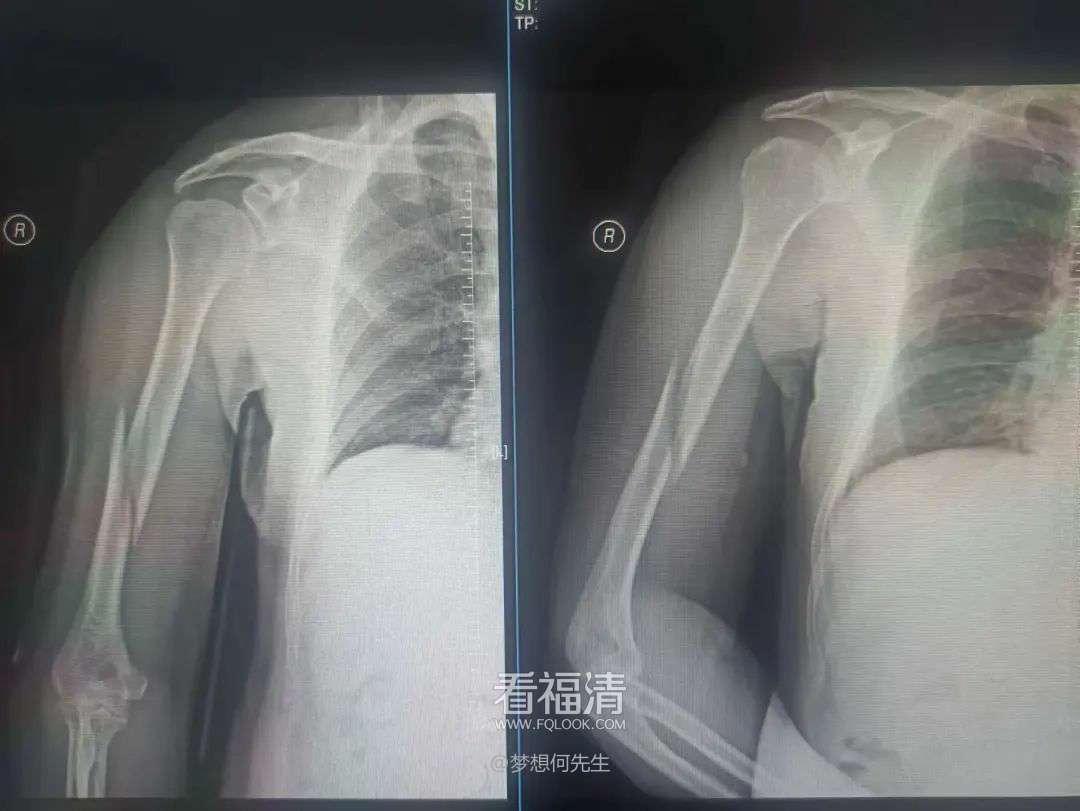

患者为53岁男性,因不慎跌倒,右上臂遭受重创,出现明显的畸形、肿痛以及活动受限。他迅速前往当地医院寻求治疗,经过详细的拍片检查后,被诊断为右肱骨干多段骨折。对此,医师原本建议通过手术治疗来确保患者的康复。然而,该患者由于患有肝硬化,导致凝血功能严重受损,无法接受手术治疗。因此,在伤后四日,患者转至福清市第五医院,希望找到更为合适的保守治疗方案。

第一次拍片

复位后拍片

王征勇接诊后,凭借丰富的临床经验,对患者的病情进行了全面而细致的评估,采用手法复位结合小夹板外固定的方式来进行治疗。随后的影像学检查复查结果显示,患者的骨折对位对线情况良好,但有一处较大的骨片出现了分离移位。王征勇再次进行了审慎的评估,认为当前的对位对线状态是适宜的,可以继续采取保守治疗措施。